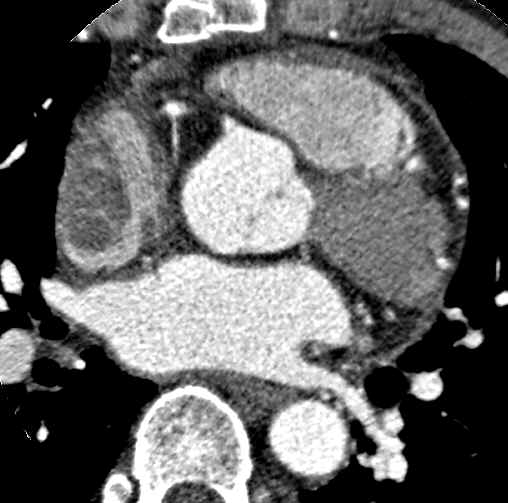

Fever, 1 month ago, 74 / M

Jong Eun Lee, Myungwon Song, Yun-Hyeon K, Chonnam National University Hospital